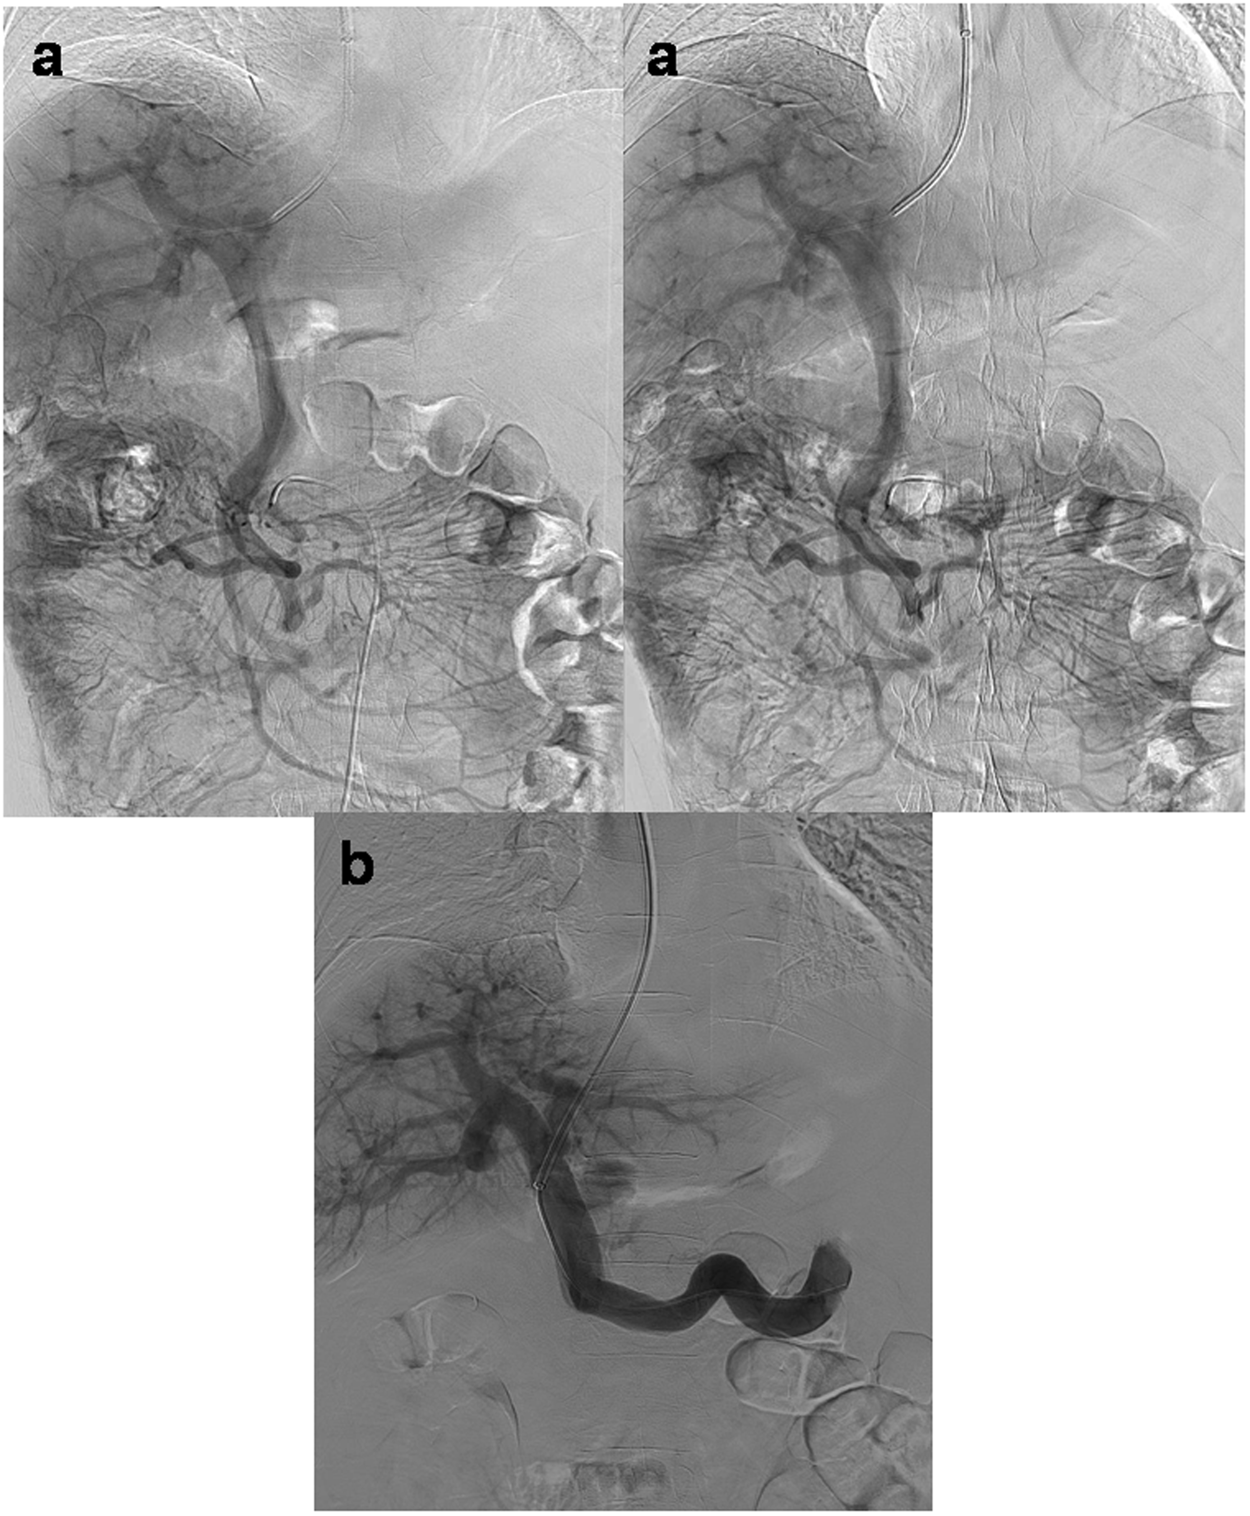

Figure 4

From: Realization of real-time X-ray stereoscopic vision during interventional procedures

(a) In a 60-year-old man with TIPS placement, duplicate X-ray images of indirect portography at different rotation angles were horizontally combined to realize X-ray stereo vision to overcome repeated puncture failure. Observation with VR glasses produced stereo vision for easily identifying spatial relationships (the left portal vein was located at the left rear of the puncture needle). (b) After the puncture angle was adjusted toward the right rear, the puncture needle successfully entered the right portal vein. The subsequent portography confirmed that the needle had entered the right portal vein toward the right rear of the previous position.